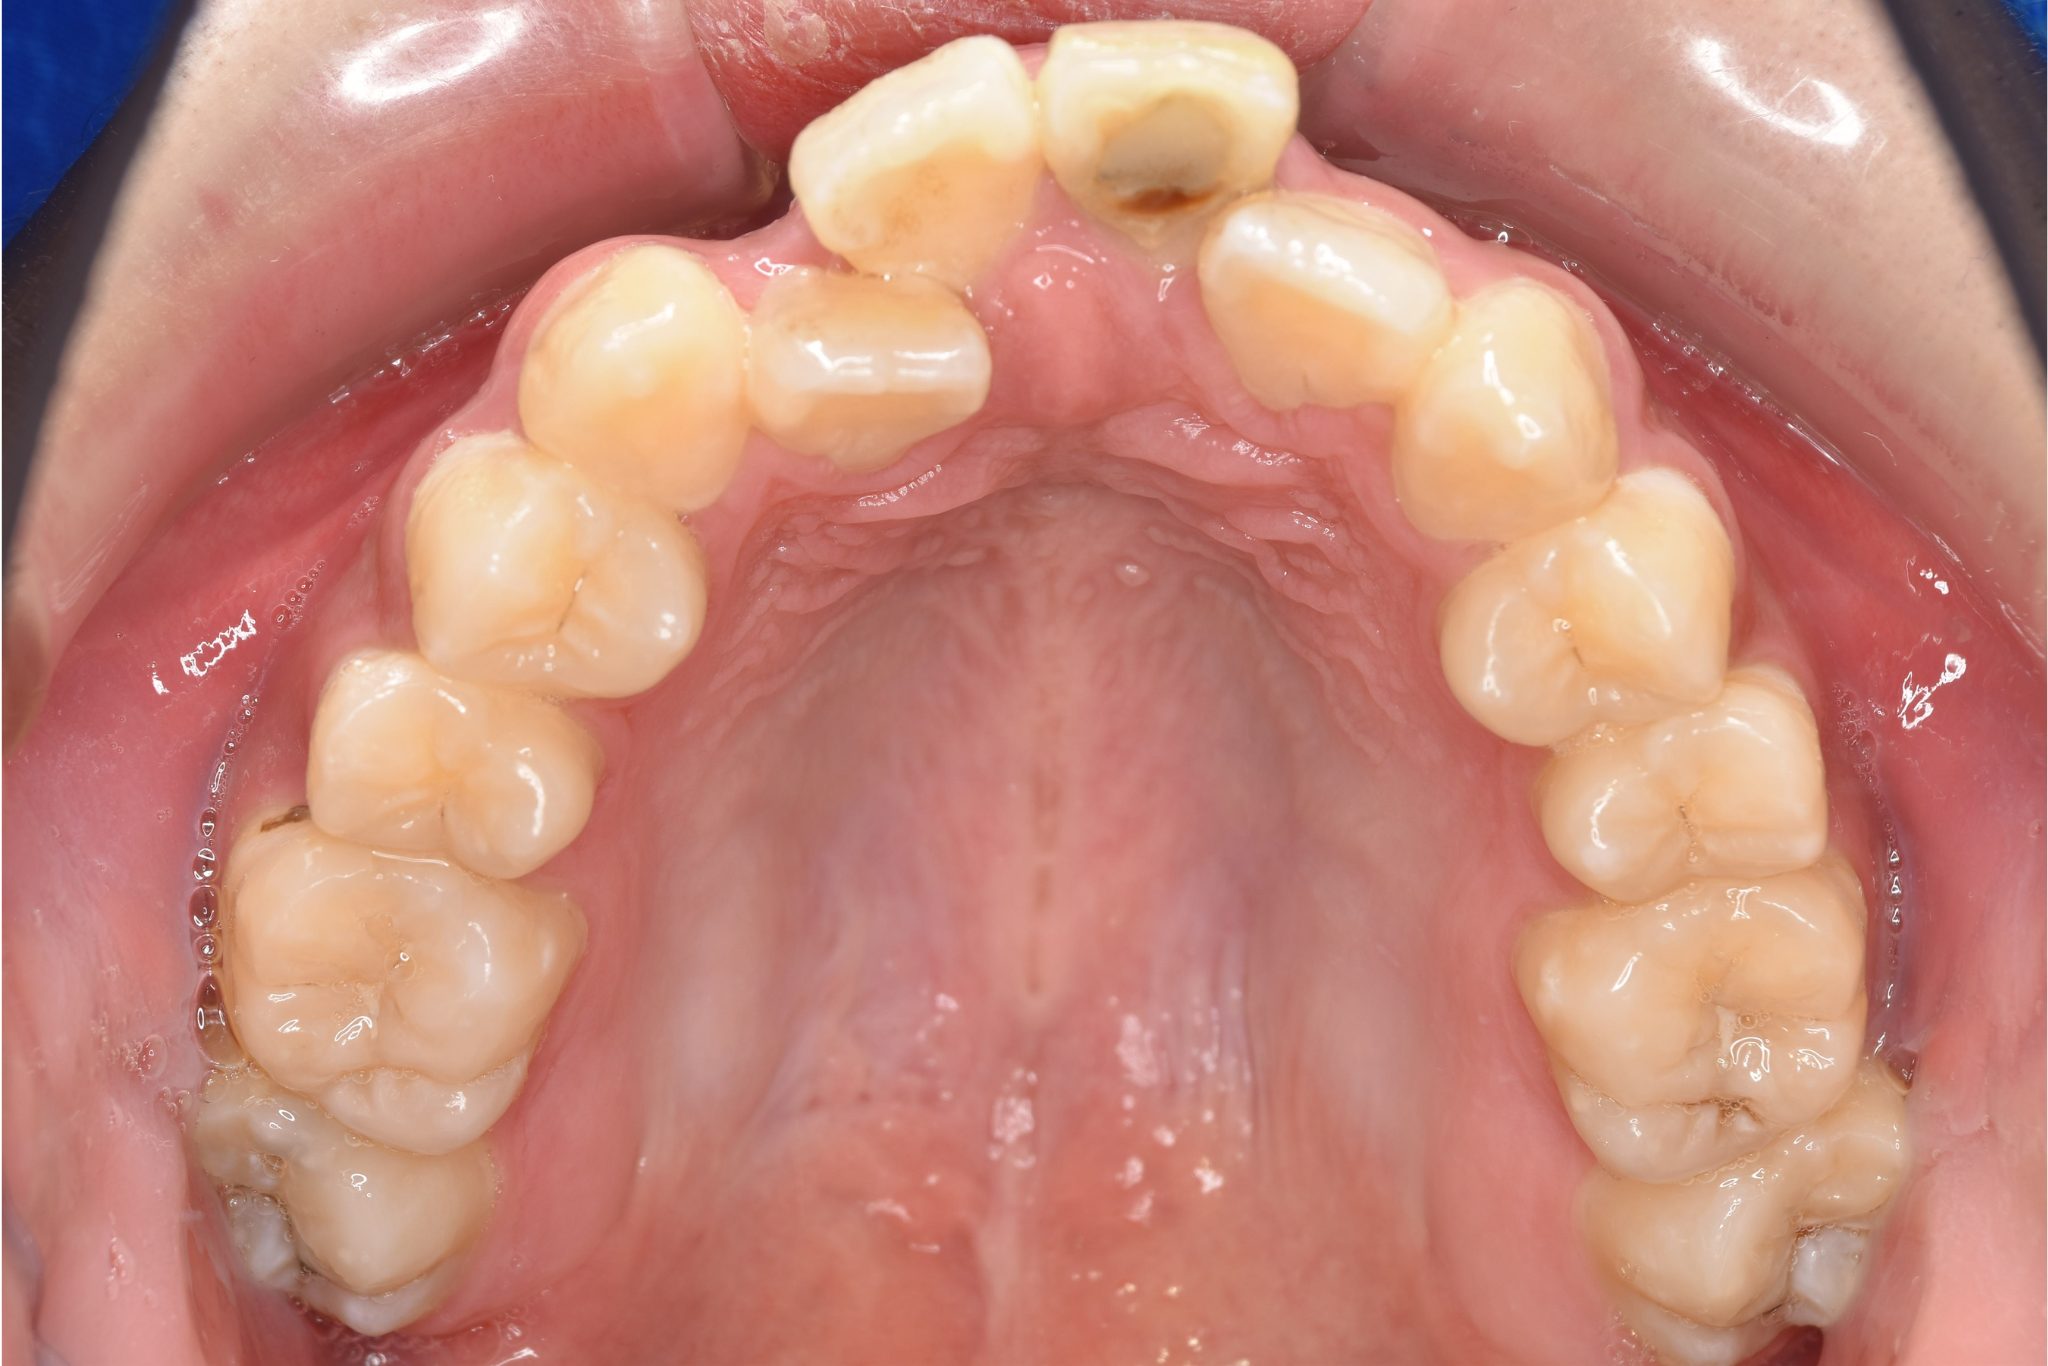

ワイヤー矯正治療|症例_037

主訴 前歯が少し前に出ている|鼻づまり

施術内容 MSEと下顎リンガルアーチを用いて上下顎骨を拡大した。

その後をマルチブラケット装置を用いて非抜歯で歯牙を配列し、良好な咬合を獲得した。

治癒期間 1年6か月間